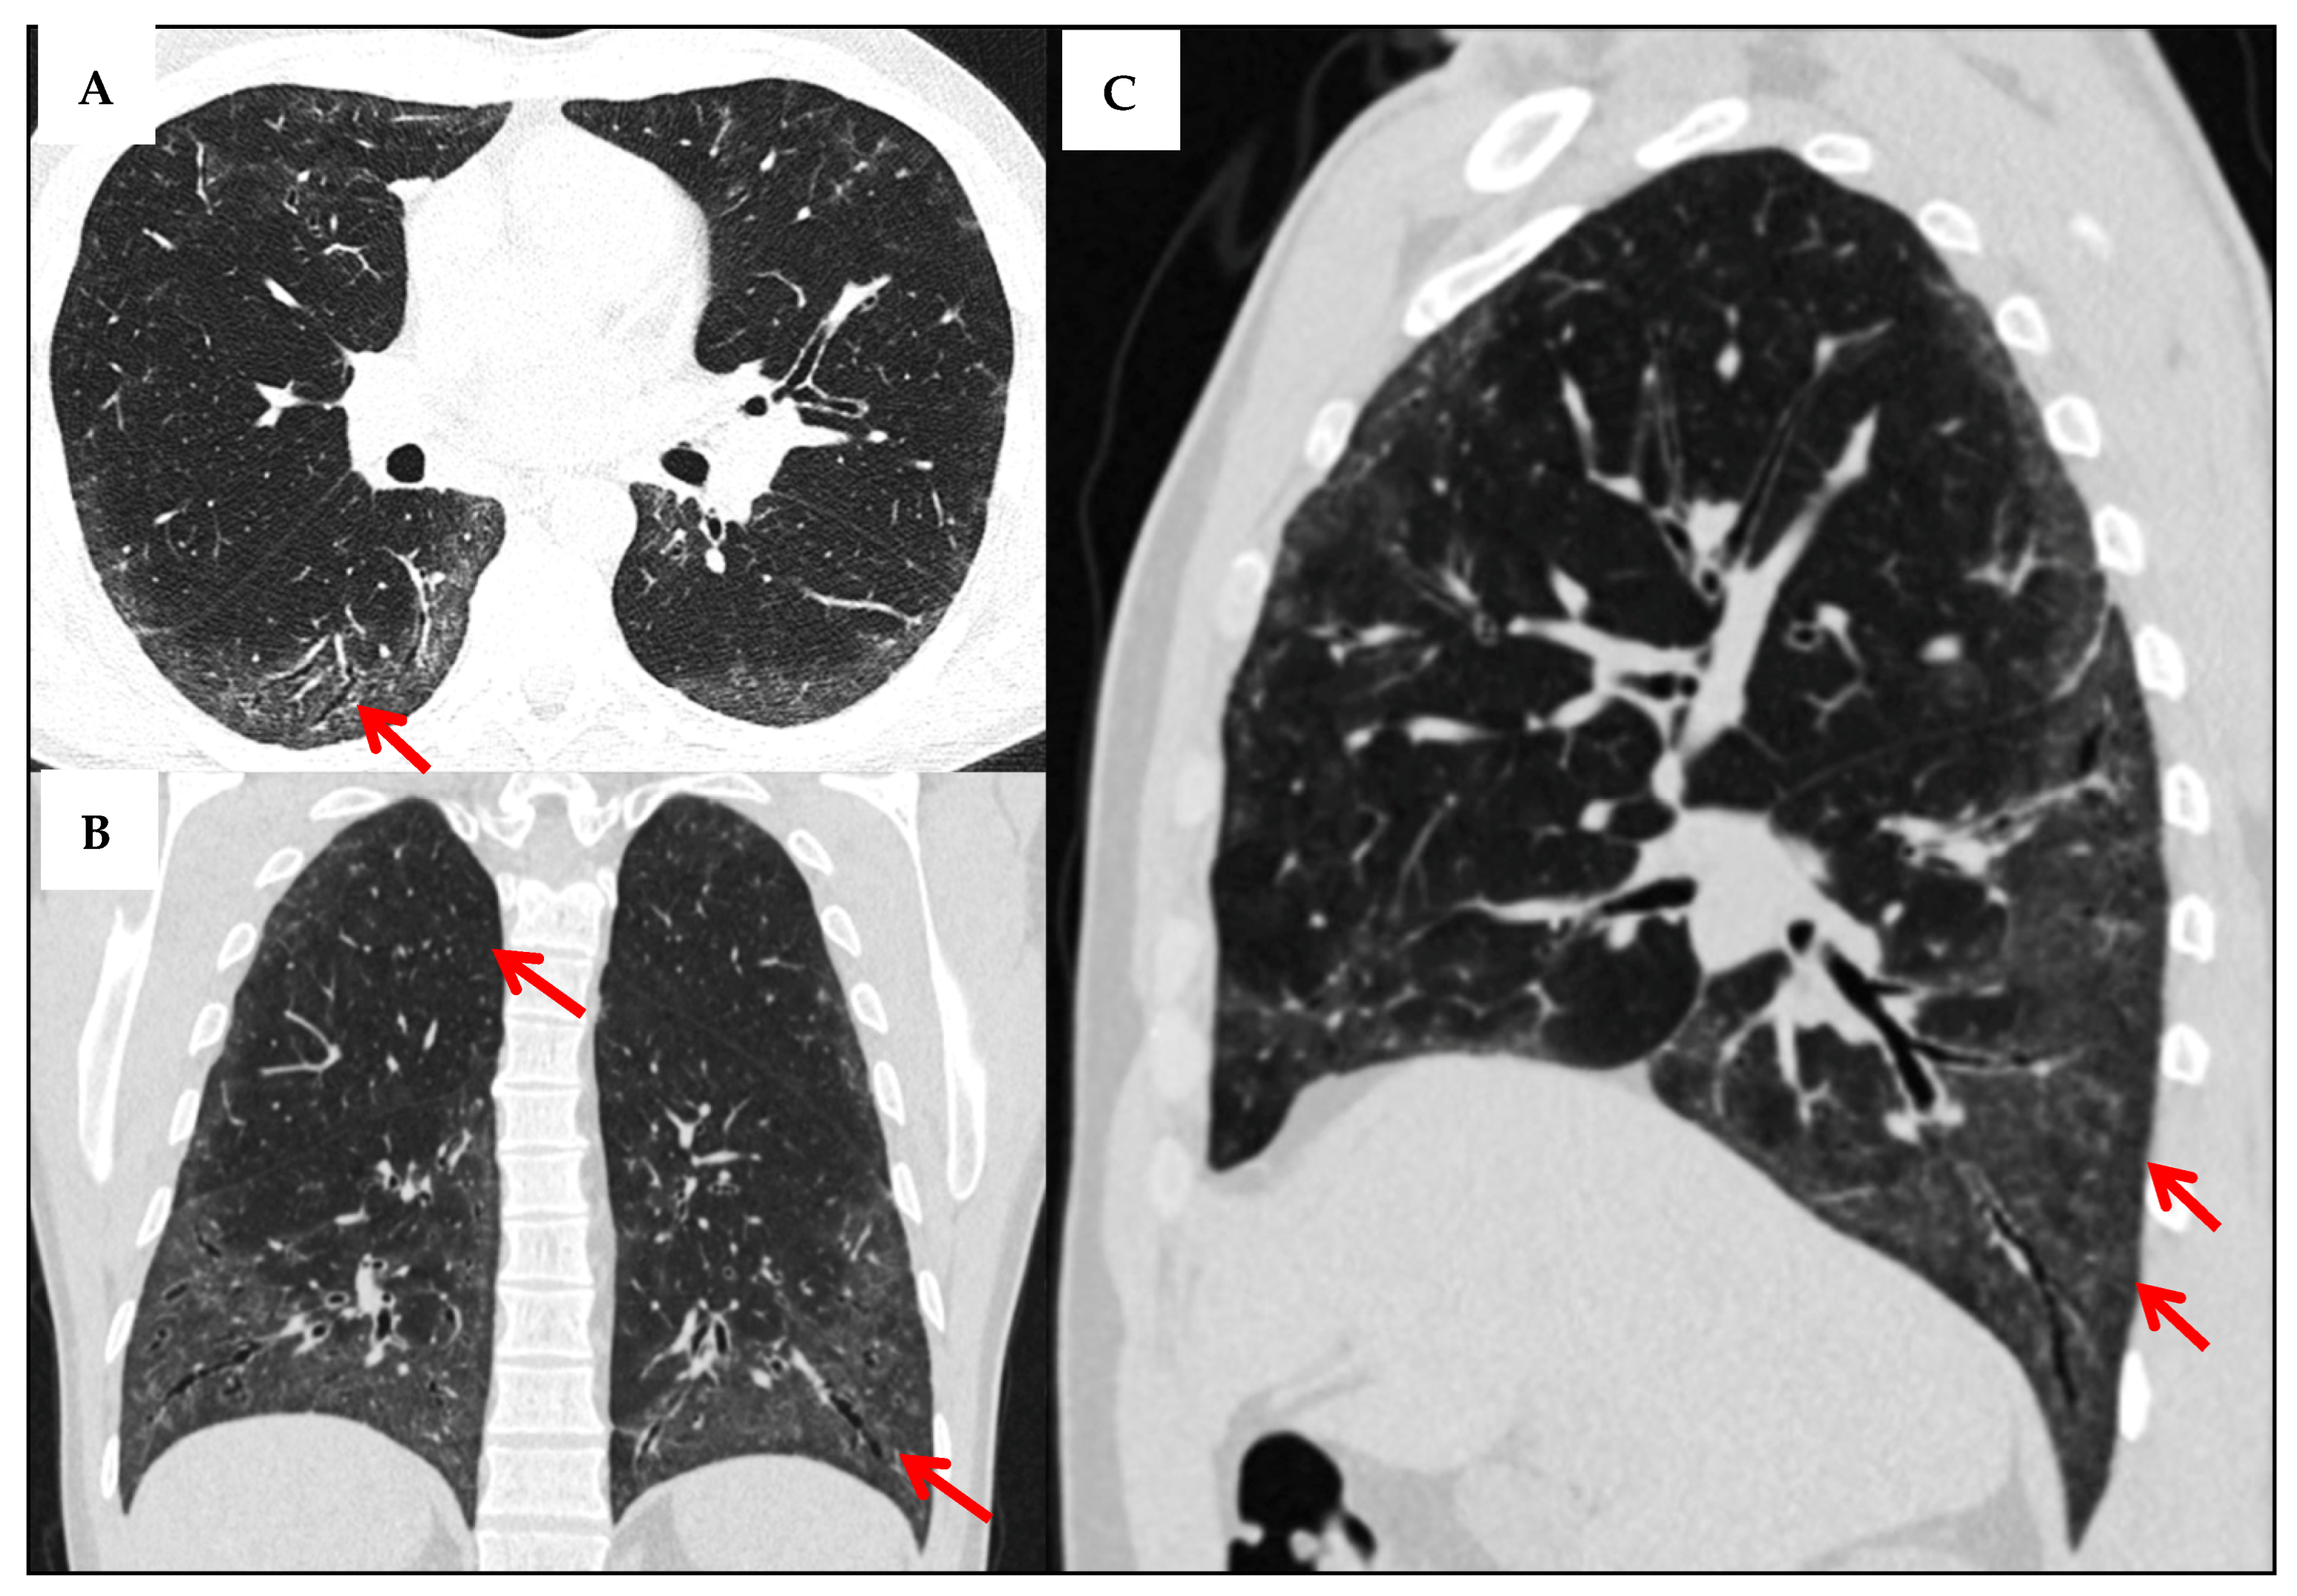

| HRCT patterns | - NSIP (42%) is most common, followed by UIP (11%), and OP/LIP (4% each).  - some studies report higher LIP prevalence (up to 17.4%). - mixed patterns (e.g., NSIP + OP/LIP) are also frequently observed.  | [21,50] |

| Other pulmonary involvement | - cystic lung disease (more common in pSS than other CTDs),  - airway-centered abnormalities (centrilobular nodules, tree-in-bud), bronchiectasis, air trapping, mosaic attenuation—often linked to follicular or constrictive bronchiolitis.  | [21,46,47,48] |